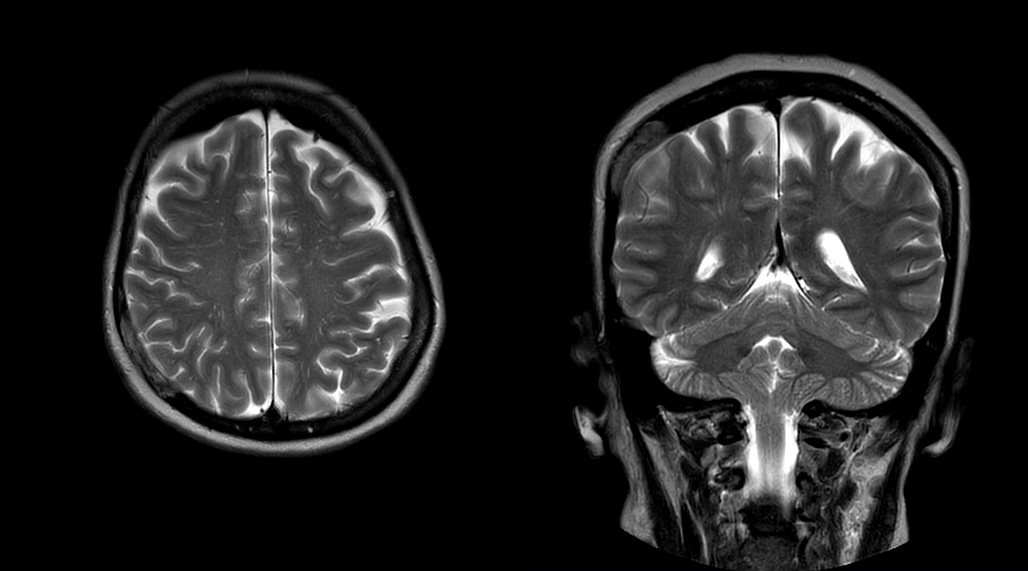

Patrick Duffy BS, RT (R) MR is Lead Technologist at DMG. “We are getting phenomenal image quality on all types of exams,” he says. “Our MSK is stellar, and so is our abdominal work. Ingenia excels at feet, hands and fingers. We do enterographies with great results. With the combination of the 3.0T magnet and the digital coils, we are able to scan prostates without an endorectal coil while still obtaining high quality results. This is a comforting experience for our male patients. We scan many obese patients, and the Ingenia does a tremendous job because of MultiTransmit, which reduces dielectric shading for more confident diagnosis. Our technologists really enjoy scanning on the Ingenia. We also have ordering physicians who specifically want their patients scanned on the Ingenia because of the results of our imaging.

“Obviously, the diagnostic capability is most important,” says Dr. Kaakaji. “Ingenia’s image quality is excellent and in follow-up studies, Ingenia provides good consistency between scans.

“Without using an endorectal coil we do our prostate MR at 0.5 mm resolution, following the European society of urology protocol [1]. For certain joints we use a virtual arthroscopy protocol with 1 mm pixel size and 2 mm slice thickness. Ingenia really excels in our neurography, brachial plexus and prostate scans. Our neurologists insist on using our 3.0T for those,” Dr. Kaakaji adds.

“The image quality is phenomenal. Robust, clear, homogenous, not obscured by dielectric shading,” adds technologist Ryan Sybesma, RT (R) MR. “Ingenia is a high performance workhorse.”